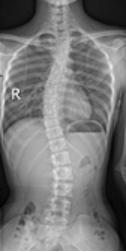

保护“未来脊梁”——关注青少年脊柱侧弯

保护“未来脊梁”——关注青少年脊柱侧弯保护“未来脊梁”---关注青少年脊柱侧弯你家孩子是否写作业时老是扭动身体?经常感觉腰背酸痛?双肩不一样高?频繁出现领口不平?裙摆不在同一水平线上?究竟是什么原因引起的?大家要警惕,有可能是青少年脊柱侧弯惹…51吃瓜网详情 +